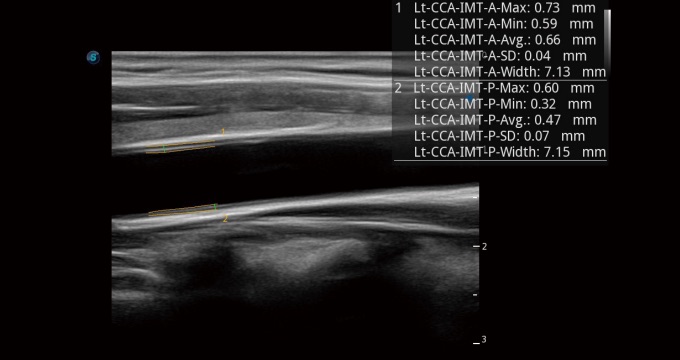

血管內(nèi)中膜的厚度值是預(yù)測(cè)心血管疾病風(fēng)險(xiǎn)的重要指標(biāo),Auto IMT可以實(shí)現(xiàn)血管近場(chǎng)和遠(yuǎn)場(chǎng)內(nèi)中膜厚度的自動(dòng)測(cè)量,為臨床提供快捷有效的診斷工具。